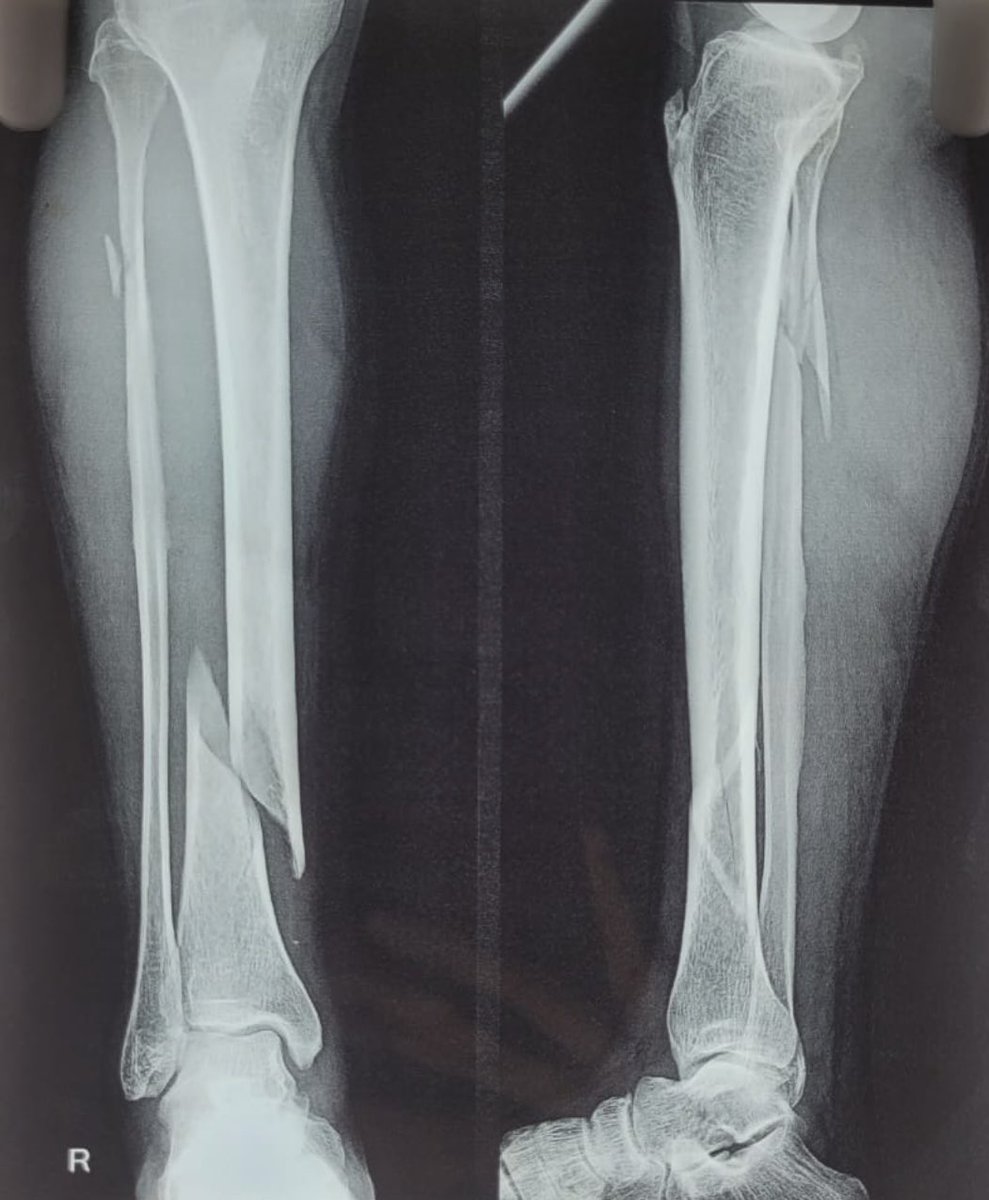

@drrajdeeproy operated on a complex proximal tibia fracture ( Shatzkar Ty Vl ) A planned and good physio is an integral part of treatment procedure and it helps achieve desired result in such fractures ! @BritOrthopaedic @AAOSAdvocacy @IndianOrthAssoc ROM at 6 was 👇

Biological fixation achieved by @drrajdeeproy and team. MIPPO ( Minimally Invasive Percutaneous Plate Osteosynthesis ) in a70yr/M. Benefits : Micro incision Early recovery Less hosp stay Early return to work. @AAOSAdvocacy @BritOrthopaedic @IOA